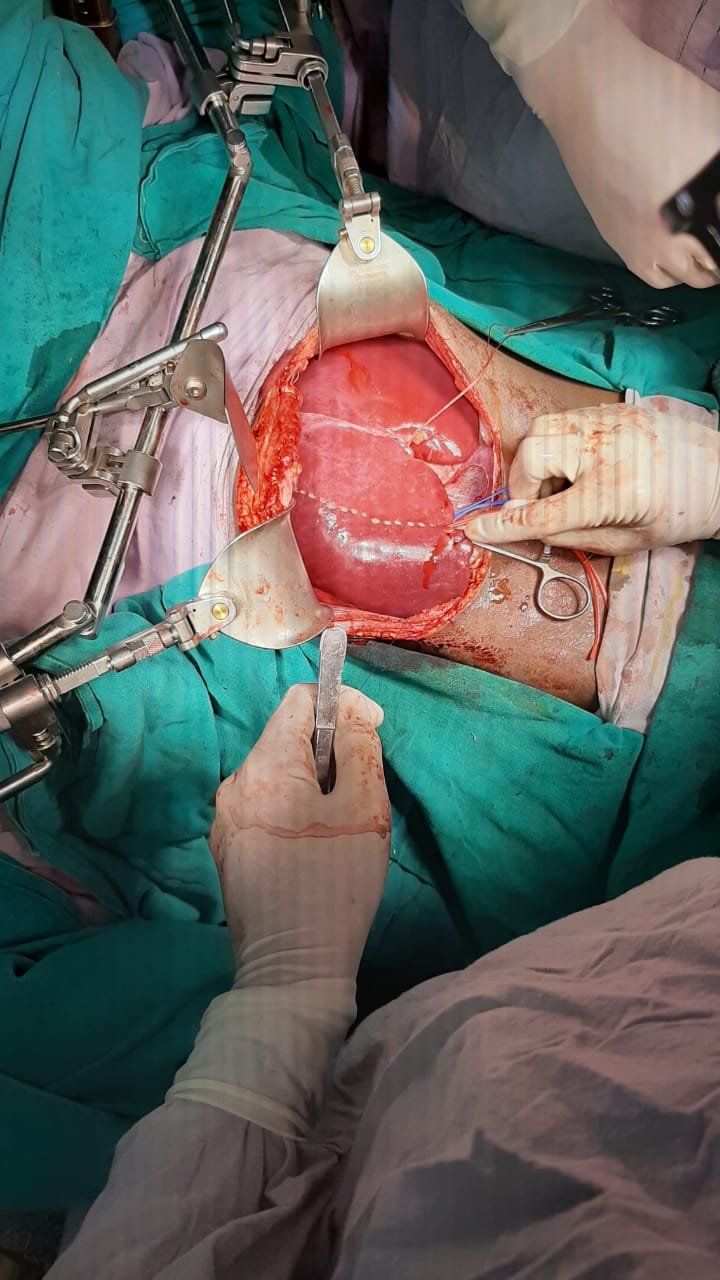

Liver Surgery

The liver is responsible for many critical functions related to metabolism, protein synthesis, bile secretion and detoxification. When it become diseased or injured, the loss of those functions can cause significant damage to the body. Liver disease is also referred to as hepatic disease. Usually, more than 75% or three quarters of liver tissue needs to be affected before a decrease in function occurs.

Liver is also unique anatomically as it looks one organ from outside it is divided in 8 segments and has 4 different type of vessel systems running inside. Removing a part of liver without damaging the function of remaining part, requires a great planning surgical precision, advance instruments and lots of experience.